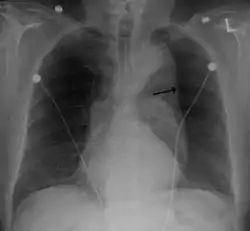

Thoracic aortic aneurysm (TAA) is an aortic aneurysm that occurs above the diaphragm.[4] Initially there are generally no symptoms.[2] Occasionally chest pain, shortness of breath, superior vena cava syndrome, or hoarseness may occur.[2] Complications may include aortic dissection, aortic regurgitation, or aortic rupture.[2]

Risk factors include high blood pressure, smoking, family history of the condition, bicuspid aortic valve, and connective-tissue disorders.[2][3] About 20% of those affected have a family history.[3] Less common causes include syphilis, arteritis, and following major trauma.[2][3] Diagnosis is generally by CT scan.[2]

Thoracic aortic aneurysm newly occurs in about 1 in 10,000 people a year.[2] About 0.25% of people are currently affected.[2] Males are affected more often than females.[2] Detection most commonly occurs in peoples 50s and 60s.[2] It is less common than abdominal aortic aneurysm.[3] The condition was first described in the 1500s by Andreas Vesalius.[5] Successful surgery was first completed in 1953.[6]